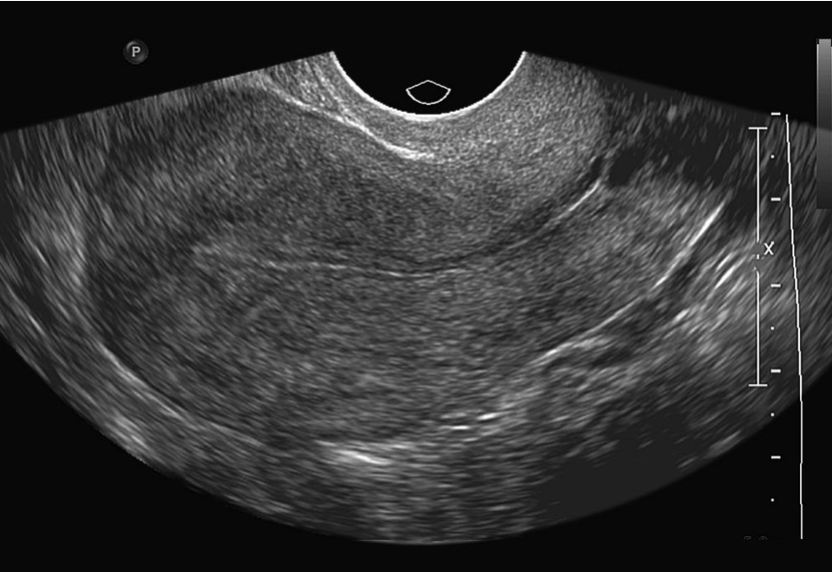

Ультразвуковое исследование (УЗИ) является наиболее простым и доступным методом оценки состояния органов малого таза. В диагностике патологии эндометрия УЗИ обладает высокой чувствительностью.

У большинства женщин в постменопаузе на фоне терапии тамоксифеном отмечается утолщение эндометрия до 9–13 мм (против 4–5,4 мм в норме) с наличием множественных кист. Выявление на УЗИ утолщенного эндометрия при отсутствии каких-либо симптомов зачастую является поводом для выраженной тревоги и проведения инвазивных диагностических процедур с биопсией эндометрия, неоднократных на протяжении всего периода гормонотерапии, что нередко приводит к необоснованной отмене препарата. При этом, независимо от определяемой на УЗИ толщины эндометрия, морфологически у 50–70% пациенток диагностируется атрофия эндометрия или клинически не значимая простая гиперплазия. Рак эндометрия при этом может выявляться при любой толщине эндометрия, в том числе и нормальной. До начала терапии тамоксифеном рекомендуется обязательное гинекологическое обследование. Женщины в пременопаузе, с учетом крайне низкого риска развития рака эндометрия, при отсутствии жалоб должны проходить лишь обязательные ежегодные гинекологические осмотры. Женщинам в постменопаузе гинекологические осмотры рекомендуется дополнять УЗИ-исследованием. Любые кровянистые выделения из половых путей у женщин, получающих тамоксифен, должны являться основанием для тщательного обследования. Выявленная гиперплазия эндометрия с наличием клинических проявлений служит поводом для смены гормонотерапии.